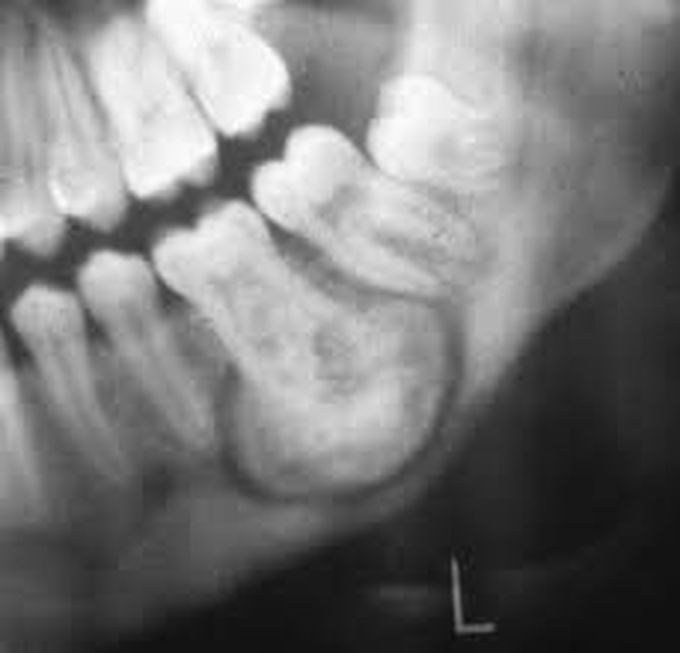

Cementoblastoma

Cementoblastoma, or benign cementoblastoma, is a relatively rare benign neoplasm of the cementum of the teeth. It is derived from ectomesenchyme of odontogenic origin. Cementoblastomas represent less than 0.69–8% of all odontogemic tumors.